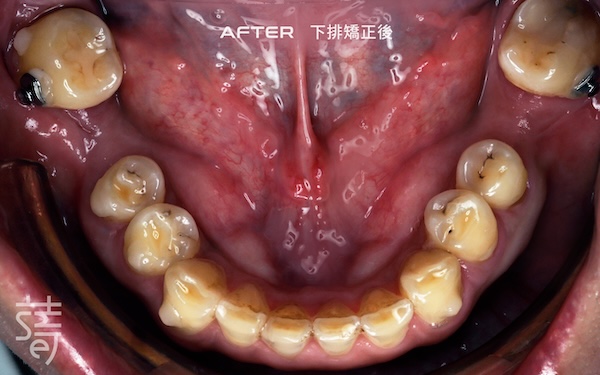

將牙齒重新排列整齊,調整上下咬合,把原本傾倒的第二大臼齒推回正確位置,為後續植牙和假牙重建打好基礎。

Teeth were realigned, the bite adjusted, and the previously tilted second molars repositioned, laying a solid foundation for implants and prosthetics.